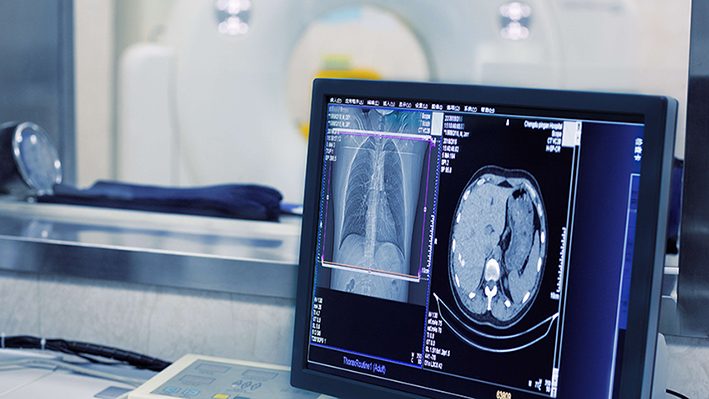

وتستطيع منصة AIMEDIC الذكية التي تستخدم خوارزميات الذكاء الاصطناعي المتقدمة، لا سيما في مجالي التعلم الآلي والتعلم العميق، تحليل صور تصوير الثدي بالأشعة السينية بدقة. وتساعد هذه المنصة أخصائيي الأشعة على تشخيص أمراض الثدي مبكراً وبدقة أكبر من خلال تحديد التلف أو المضاعفات الخفية في أنسجة الثدي.

و بالإضافة إلى تحليل الصور المستلمة من أجهزة التصوير الطبي باستخدام نماذج متقدمة، يقوم هذا المنتج أيضاً بالإبلاغ بانتظام عن نتائج النظام في بيئة منظمة تسمى “وحدة التقارير” حتى يتمكن أخصائي الأشعة من تقديم تحليل أكثر دقة.